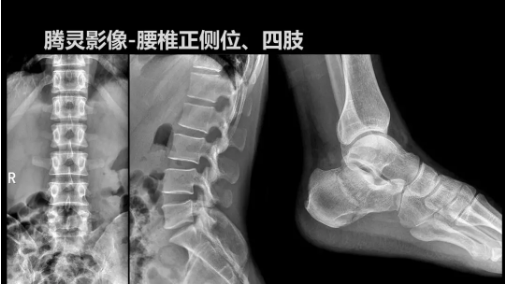

2019年10月19日,82屆秋季CMEF于青島世博城國際展覽中心如期舉辦,國內(nèi)動態(tài)DR領域的佼佼者安健科技攜新品——“騰靈”多功能診斷專用動態(tài)DR亮相展會現(xiàn)場。

“騰靈”是安健科技的第四代動態(tài)DR產(chǎn)品,可實現(xiàn)全科室應用。如各類常規(guī)的X線檢查、消化道檢查、骨科檢查、婦科、兒科檢查等。此外,安健科技為“騰靈”在真正意義上實現(xiàn)多科室、多功能診斷進行了多項針對性設計。

相較前代產(chǎn)品,“騰靈”在圖像質量方面得到了全面升級,“騰靈”采用17*17非晶硅平板探測器設計,采集矩陣達3072*3072,動態(tài)范圍達16bit,為成像提供超大視野的同時保證成像質量,此外,該款機型可根據(jù)醫(yī)療機構的差異化需求而選配不同的動態(tài)平板探測器,以此來適應不同階層用戶所需。